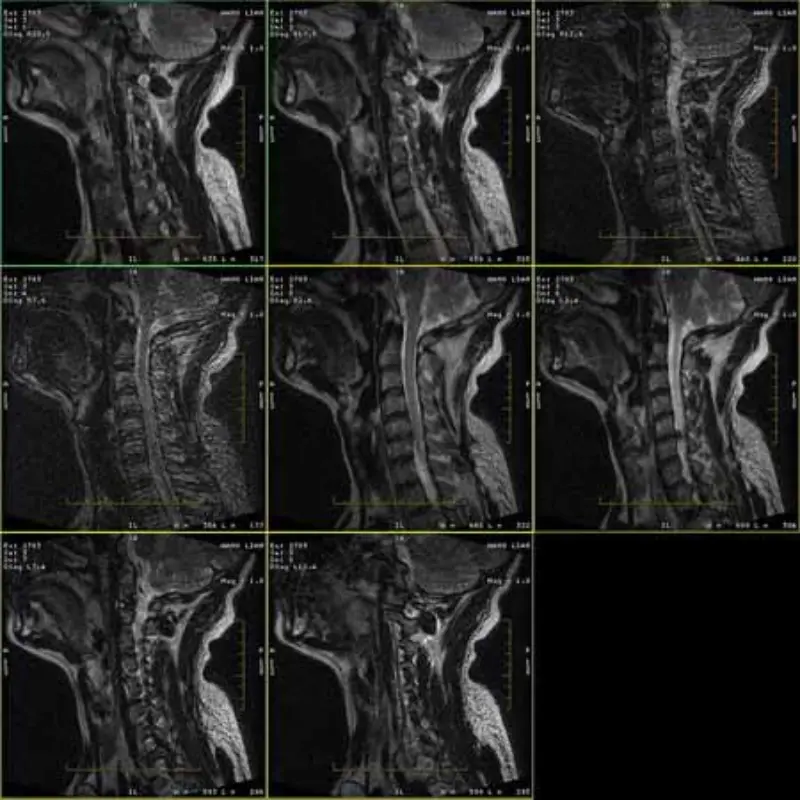

Billederne af FRFSE- og GRE-protokollerne har spøgelsesbilleder, og nogle gange vises billeder med lav SNR i én serie. Men SE-protokolbilleder er normale.

Se venligst vedhæft billeder.

1. Disse artefakter forekommer kun i billedet af FRFSE- og GRE-protokoller, men SE-protokol